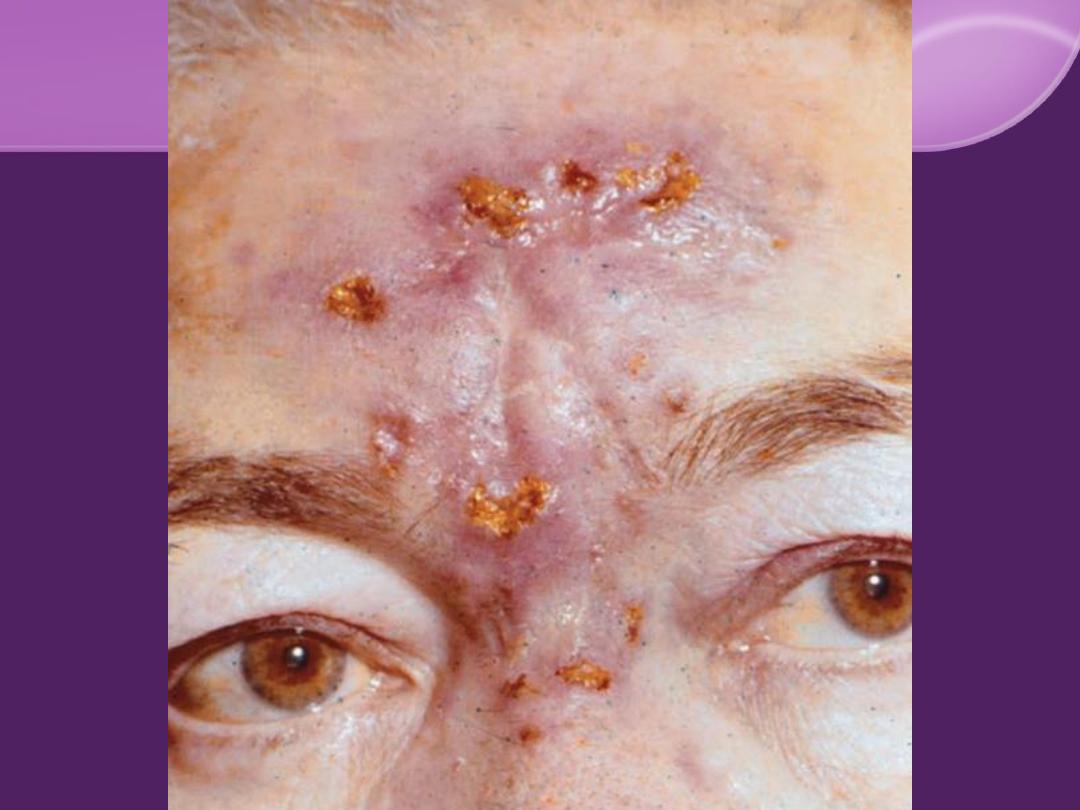

Tertiary Syphilis:

Cutaneous Lesions:

In opposite to the secondary syphilis;

few

,

few MO,

asymmetrical, slowly growing, destructive and heals

with scar.

1. Nodular and noduloulcerative lesions

2. Gummas (a form of granuloma)